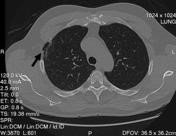

Şəkil

Kliniki müayinə zamanı döş qəfəsi divarında yumşaq konsistensiyalı, tənəffüs aktı zamanı ölçüsünü dəyişən, ağrısız şişkinlik müəyyən olunur. Rentgenoloji müayinə zamanı diaqnozu təsdiqləmək olur. Şübhəli hallarda KT müayinəsi çox faydalıdır, defektin ölçüsünü müəyyən etməyə imkan verir.